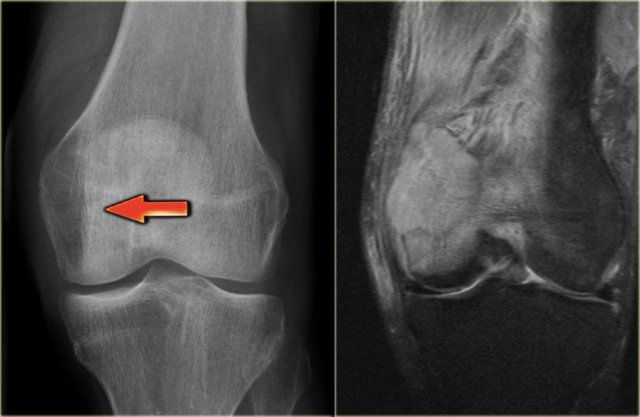

On the left a giant cell tumor of the distal radius with ill-defined margins, destruction of the subchondral bone plate and extension towards the soft tissues.

On the right a giant cell tumor in the proximal tibia with somewhat better defined margin and non-interrupted cortical bone.